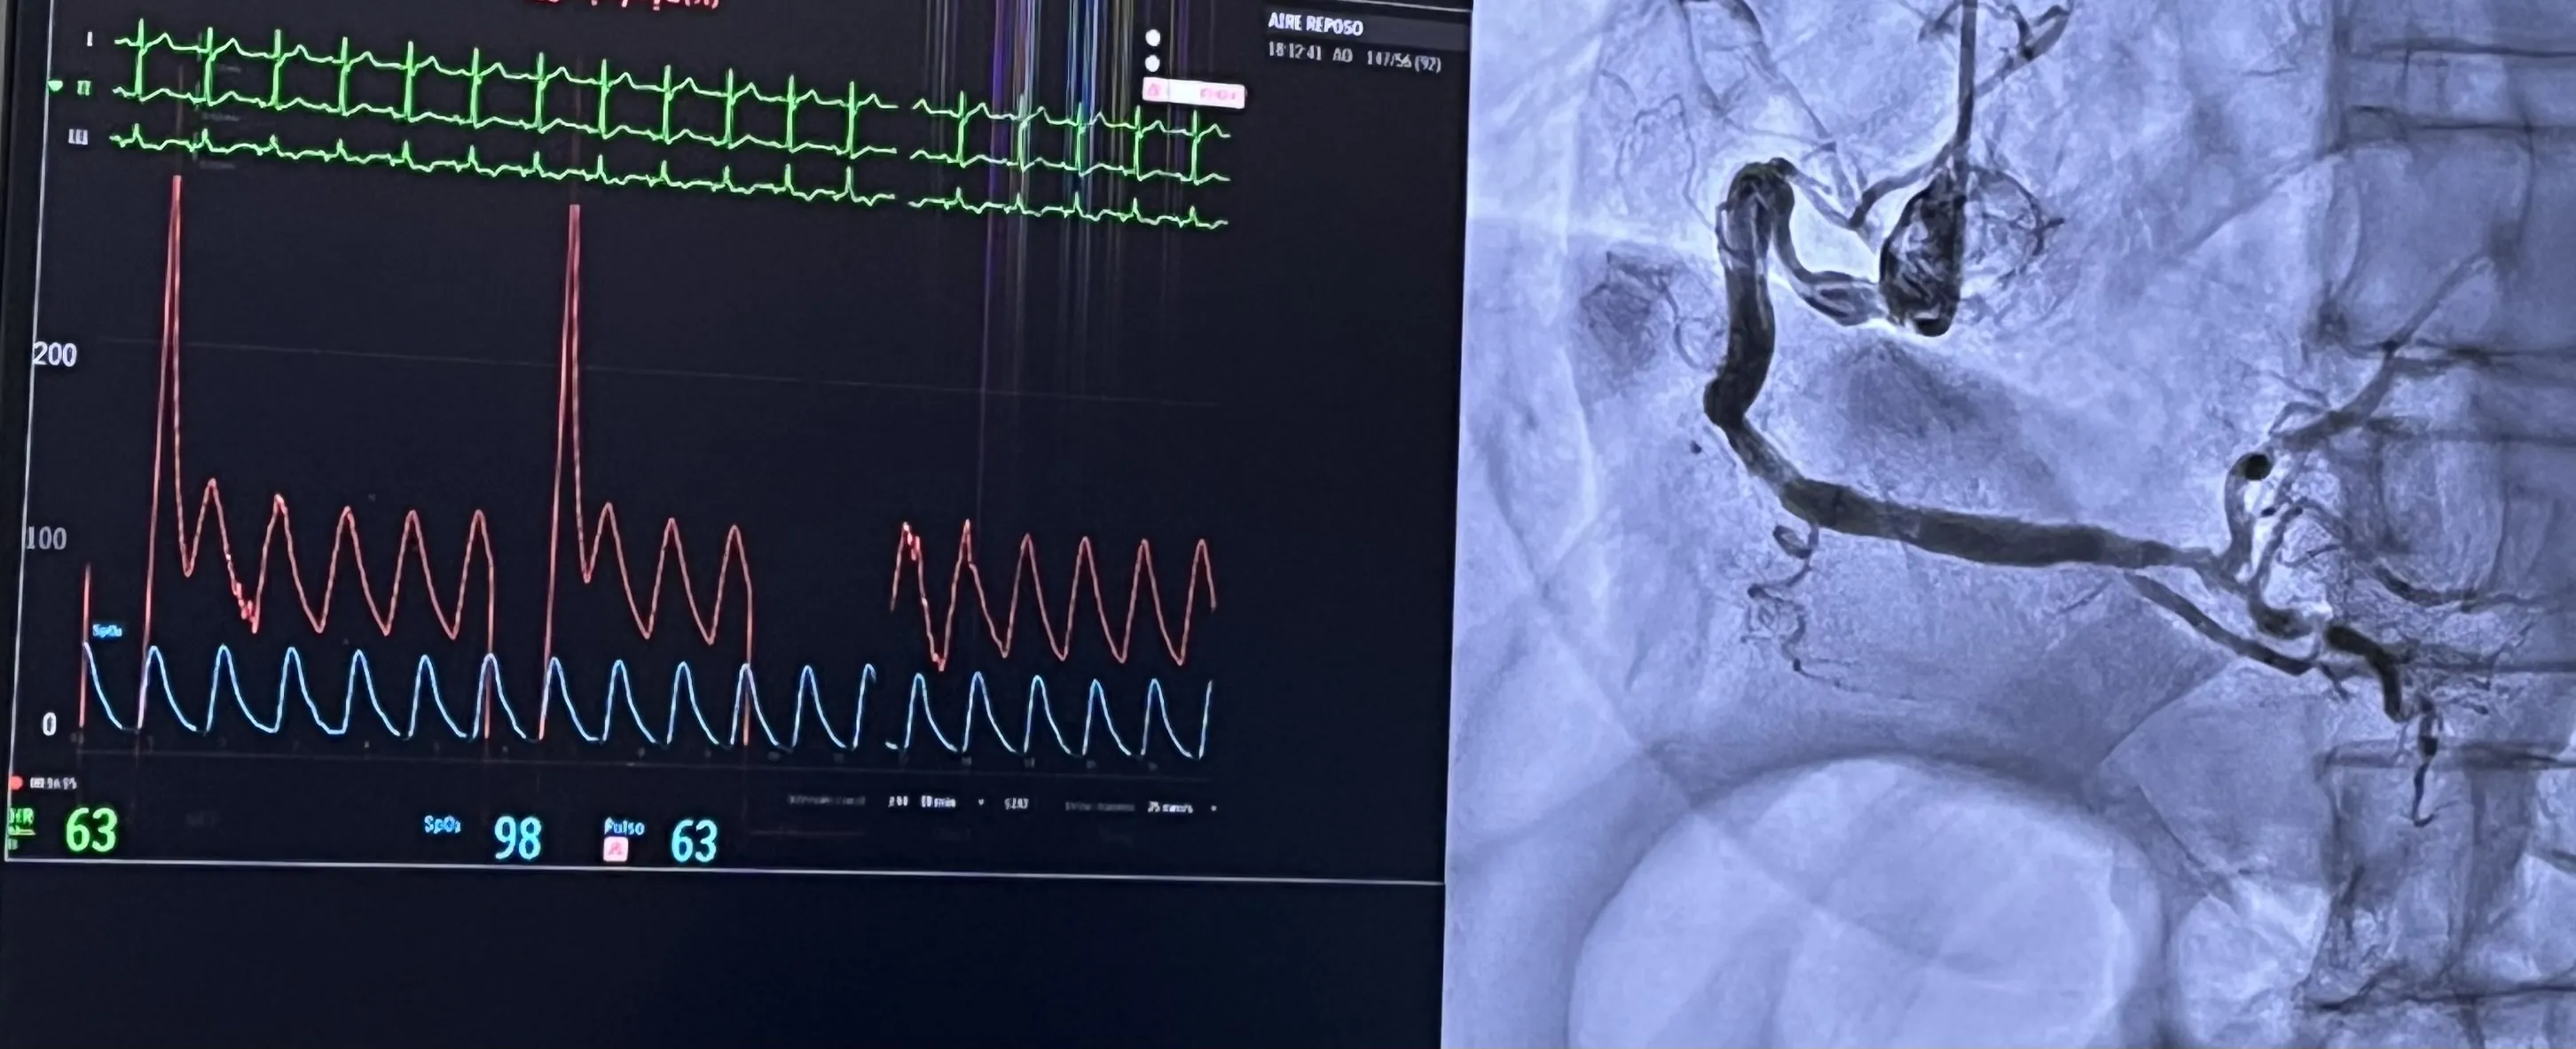

Cateterismo cardíaco izquierdo por vía radial: visión práctica

Una guía detallada sobre el procedimiento y sus beneficios en la cardiología moderna